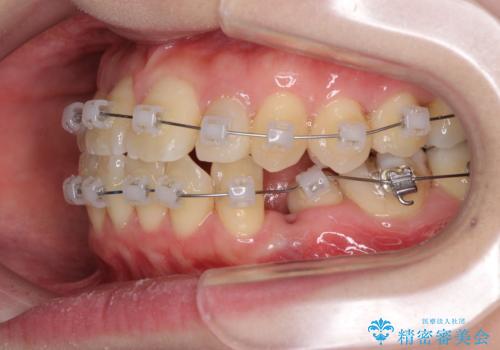

- 矯正装置

- クリアブラケット

抜歯矯正は2年から2年半程度の治療期間を要することが一般的ですが、僅か1年1ヶ月で終了しました。

あっという間に気になっていた歯並びが改善し、患者様には大変満足していただきました。